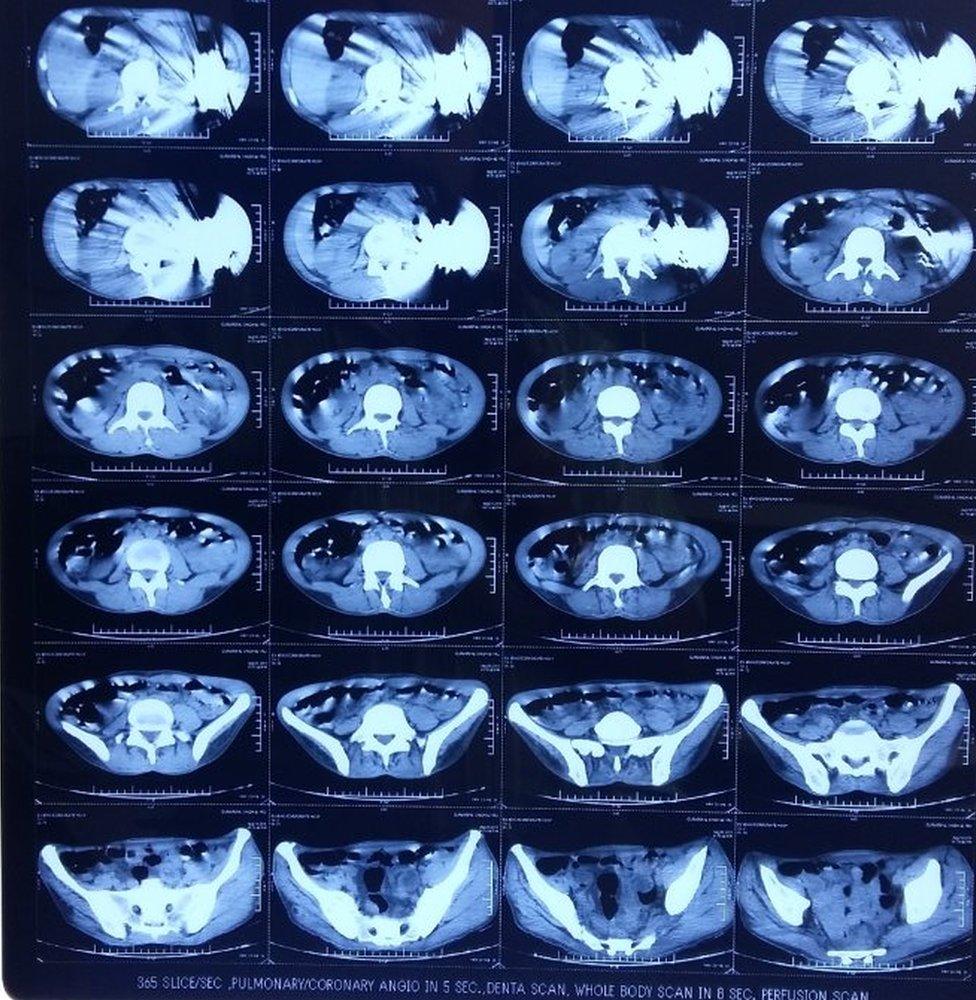

CT scans showed 40 knives in the man's stomach